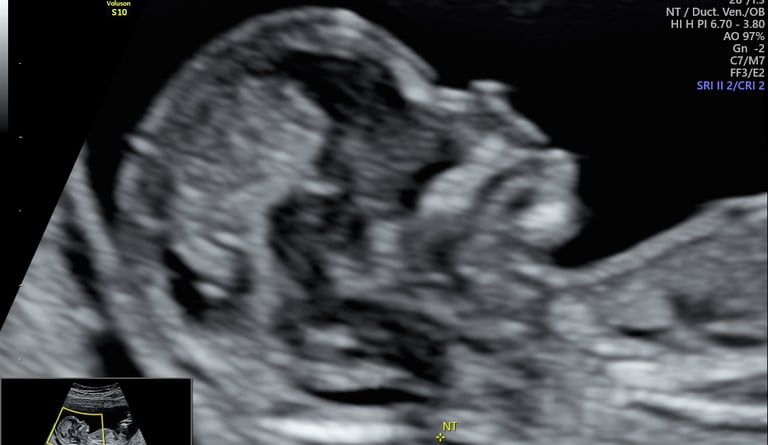

ecografía morfológica primer trimestre (genética y más)

12 - 14 semanas